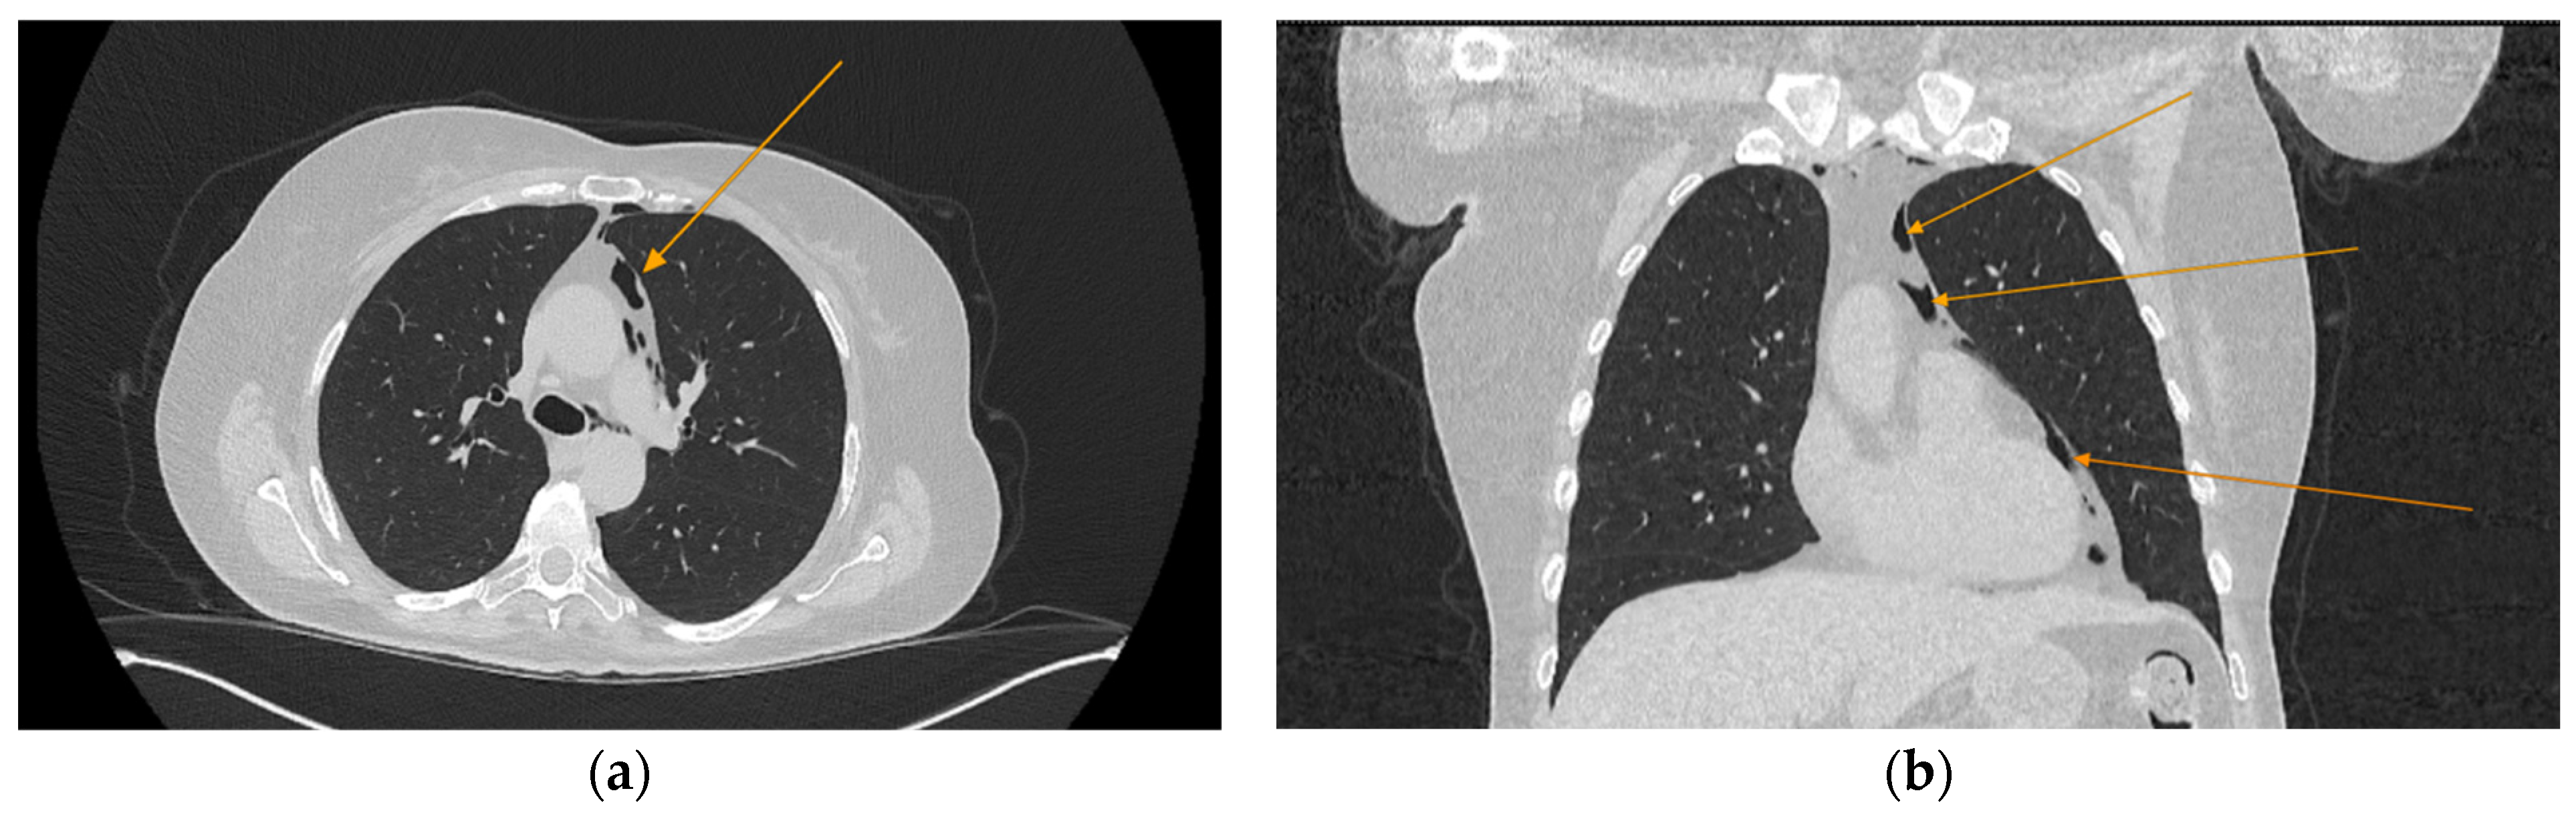

The chest CT scan performed in the emergency department (Figure 1) revealed the presence of pneumomediastinum. CT scans of the abdomen and pelvis were also performed, giving the high lipase and epigastric pain, revealing findings consistent with acute pancreatitis (with peripancreatic fluid collection, consistent with moderate acute pancreatitis per the modified CT severity index), as well as a solitary gallbladder stone measuring approximately 20 mm in diameter, without intra or extrahepatic biliary ducts enlargement (Figure 2).

Figure 1.

Initial chest CT scan, demonstrating pneumomediastinum (arrows): (a) axial view showing free air in the mediastinal space; (b) coronal view revealing air tracking along several mediastinal structures.